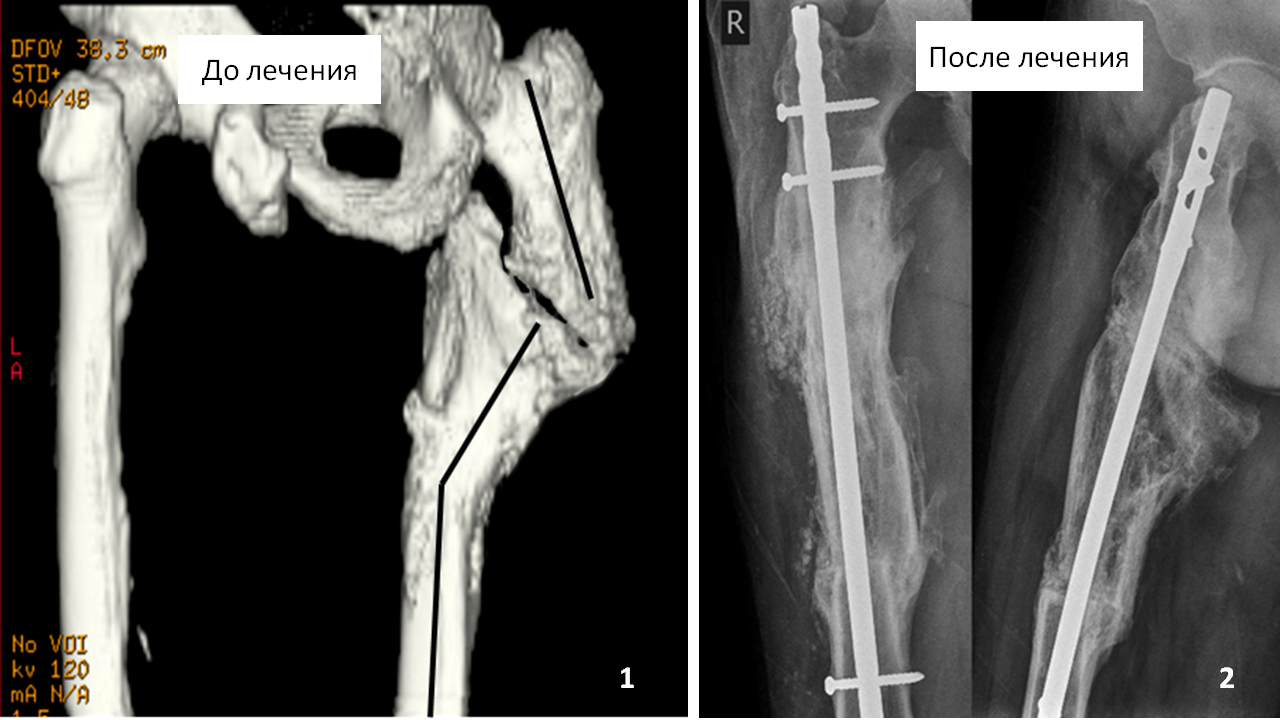

З приводу перелому правого стегна оперувався 5 разів, з них 2 рази в Москві. Однак позитивного результату отримано не було - досягти зрощення перелому і усунути деформацію стегнової кістки не вдалося. Всі 20 років пересувався за допомогою милиць. В Ізраїлі запропонували вирізати всю верхню частину стегнової кістки і поставити ендопротез кульшового суглоба на довгій ніжці.

Нами було проведено відновне хірургічне лікування з використанням клітинних технологій (аутологічних стовбурових клітин).

Через п'ять місяців після початку лікування пацієнт зміг пересуватися самостійно, повністю наступаючи на праву ногу і перестав користуватися милицями.